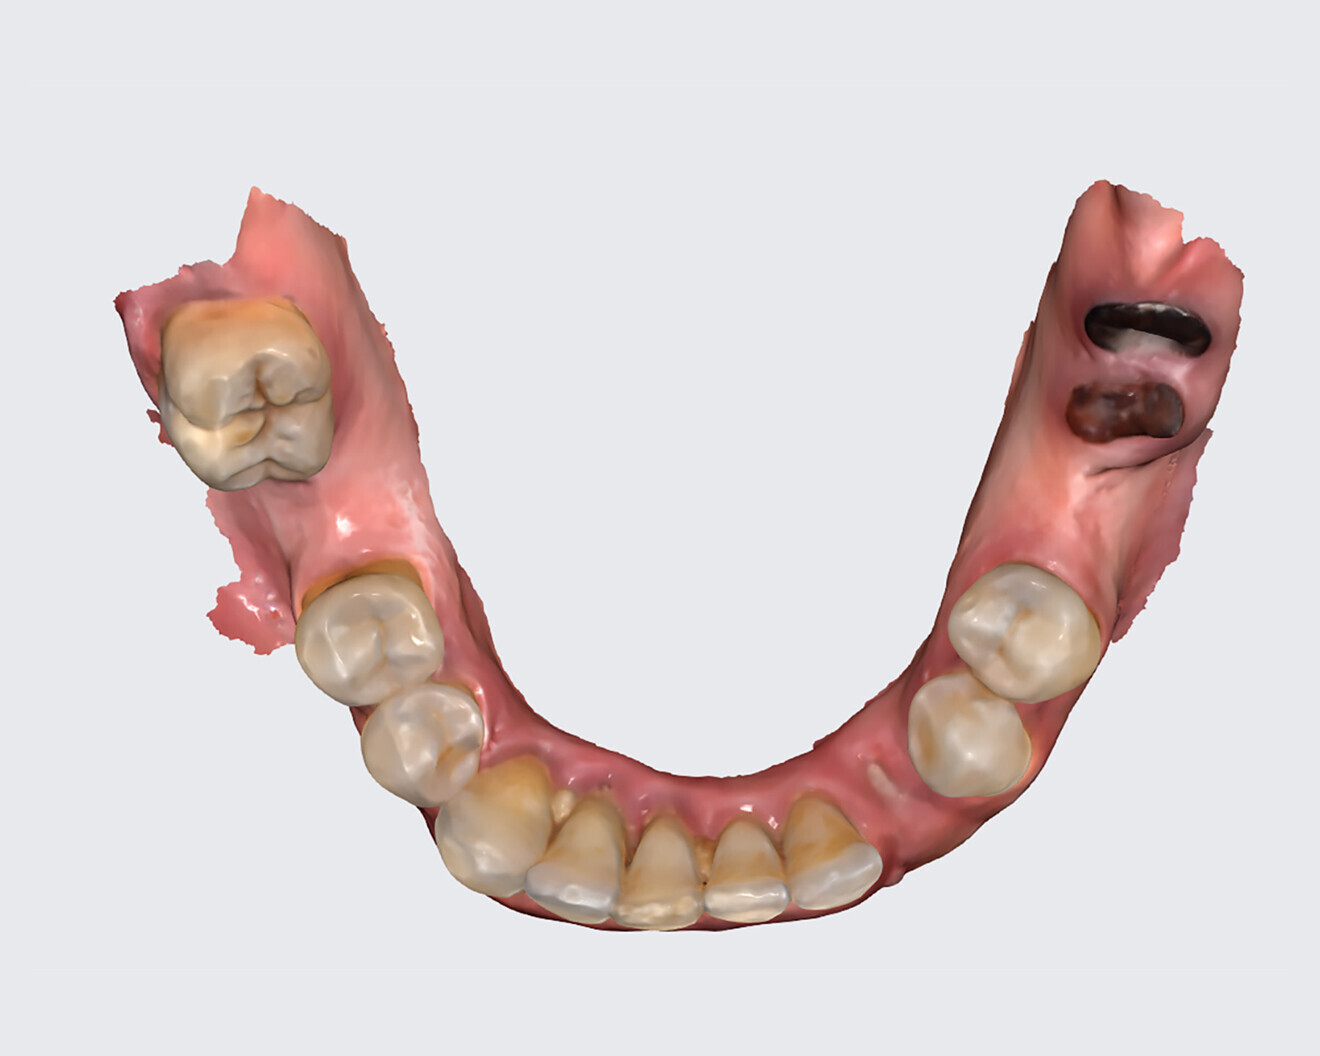

The following case exhibits the features and benefits of utilising Grammetry in combination with innovative screw technology. The 63-year-old male patient with a non-contributory medical history presented with failing dentition in both arches. Diagnostic records were collected, including full-mouth digital radiographs (RVG 6200, Carestream Dental; Fig. 11a), intra-oral scans (Medit i700 wireless; Figs. 11b & c), a large field of view CBCT scan (Carestream 9600; Fig. 11d), and intra-oral and extra-oral photographs (Fig. 11e). The mandible contained an impacted canine as well as several mobile and painful teeth. The maxilla was in a similar condition, having deteriorating, painfully mobile teeth, as well as extensive caries. While the bone loss was significant in the mandible, the vertical dimension of occlusion (VDO) allowed for both arches to be treated with an FP-1 prosthesis.

Fig. 11c: Mandibular intra-oral scan.